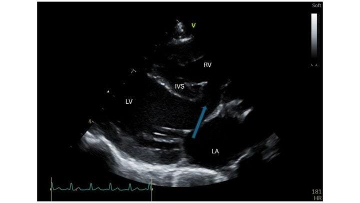

FIGURA 1 – Ecocardiografia de um defeito do septo ventricular. Onde se pode ver um defeito do septo interventricular (DSV) de grandes dimensões (seta), localizado imediatamente abaixo das válvulas atrioventriculares.

VE — ventrículo esquerdo; VD — ventrículo direito; AE — átrio esquerdo; SIV — septo interventricular.